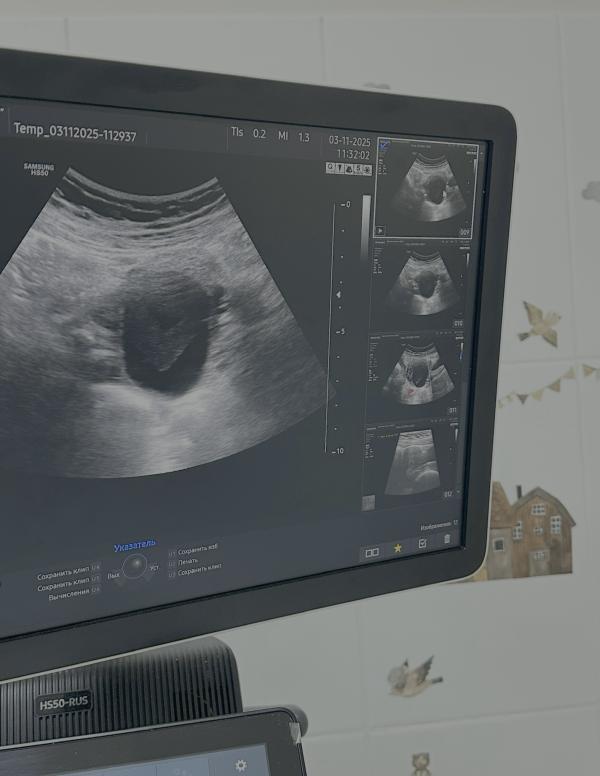

При ультразвуковом исследовании органов малого таза у нашей пациентки обнаружилось кистозное образование правого яичника размером четыре сантиметра.

P.S Если внимательно присмотреться к УЗИ-снимку, форма содержимого кисты напоминает сердце — будем считать это добрым знаком! Пусть все пройдёт хорошо, и цикл быстро восстановится 😊✨